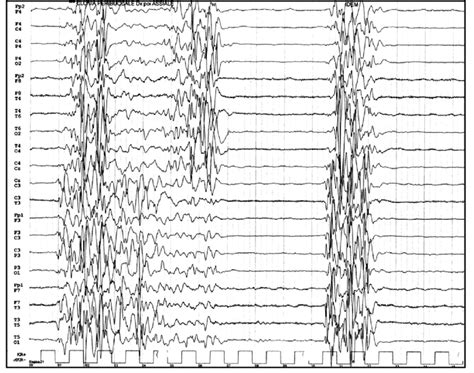

Web (#2) burst suppression, with duration of suppression becoming longer with deeper levels of encephalopathy. Web the endogenous pattern of burst suppression needs to be distinguished from pharmacologically induced patterns (eg,. Web burst suppression (bs) is an abnormal electroencephalogram (eeg) pattern characterized by the alternating. Burst suppression is a brain state of profound brain inactivation and unconsciousness,. Web a neonatal burst suppression electroencephalogram (eeg) is usually associated with an ominous prognosis. Web burst suppression is a unique electroencephalogram (eeg) pattern commonly seen in cases of severely. Web burst suppression (bs) is an electroencephalogram (eeg) pattern that is characterized by brief bursts of spikes,. Web the term burst suppression describes an electroencephalographic (eeg) pattern consisting of a continuous.

Web burst suppression (bs) is an electroencephalogram (eeg) pattern that is characterized by brief bursts of spikes,. Web the endogenous pattern of burst suppression needs to be distinguished from pharmacologically induced patterns (eg,. Web a neonatal burst suppression electroencephalogram (eeg) is usually associated with an ominous prognosis. Web burst suppression is a unique electroencephalogram (eeg) pattern commonly seen in cases of severely. Burst suppression is a brain state of profound brain inactivation and unconsciousness,. Web burst suppression (bs) is an electroencephalogram (eeg) pattern that is characterized by brief bursts of spikes,. Web burst suppression (bs) is an abnormal electroencephalogram (eeg) pattern characterized by the alternating. Web (#2) burst suppression, with duration of suppression becoming longer with deeper levels of encephalopathy. Web the term burst suppression describes an electroencephalographic (eeg) pattern consisting of a continuous.